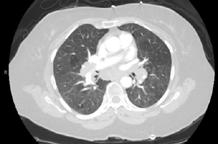

CASE PRESENTATION

A 58-year-old female with recently diagnosed COVID-19 pneumonia was found to have a dry cough and dyspnoea in the setting of persistent bilateral hilar and mediastinal lymphadenopathy associated with bilateral nodular infiltrates. Of note, she immigrated to the USA from India 10 years prior, with the most recent travel to India 2 years ago. Quantiferon testing upon return to the USA was negative at that time. Workup included bronchoscopy with endobronchial ultrasound revealing non-caseating granulomas with negative stains for acid-fast bacilli (AFB). She was diagnosed with Stage 3 sarcoidosis and initiated on prolonged steroid taper with improvement of symptoms. With taper of steroid dose, however, she developed lymphocyte-predominant exudative effusion with negative cultures, and was reinitiated on a protracted steroid course with rapid symptom resolution. At 4-month follow-up, she had worsening CT findings upon steroid taper, and was started on azathioprine. One month later, she required hospital admission for worsening dyspnoea and fatigue. She was noted to be febrile, tachycardic, and tachypnoeic with worsening

hypoxia. Subsequent CT chest showed progression of bilateral nodular infiltrates with new right upper lobe consolidation and air bronchograms concerning for multifocal pneumonia (Figure 1). Incidentally, she was also noted to have calcified splenic granulomas. She developed rapid clinical deterioration, ultimately requiring mechanical ventilation, pressor support, and continuous renal replacement therapy. Repeat bronchoscopy revealed diffuse alveolar haemorrhage with multiple AFB smears positive for Mycobacterium tuberculosis. She was immediately initiated on quadruple therapy, but unfortunately, despite treatment, developed refractory shock and passed away 2 weeks after initial presentation.

TB and sarcoidosis share synonymous manifestations, making differentiating between progression of sarcoidosis and the development of TB difficult, especially in patients who have biopsy-proven sarcoidosis. This patient’s initial negative Quantiferon testing and AFB stains, CT scan findings, pathology, and rapid symptom resolution with steroids support the initial diagnosis of sarcoidosis. Given her history and no recent identifiable risk factors, TB was lower on the differential at initial presentation to the hospital. While findings of lymphocytepredominant pleural effusions3 and splenic granulomas may be seen with sarcoidosis, this should raise suspicion for tuberculosis

A) Initial adenopathy with peripheral patchy ground glass opacities in the right lung following COVID-19 pneumonia. B) Persistent bulky adenopathy 1 year after initial presentation. C) Extensive nodularity throughout the right lung with increasing confluent opacities in the right upper lobe and stable mediastinal lymphadenopathy 2 years after initial presentation. D) Tuberculosis superimposed on sarcoidosis with progression of nodular infiltrates, worsening right upper lobe consolidation, and air bronchograms with incidental calcified splenic granulomas (not pictured).

Figure 1: CT progression of patient’s sarcoidosis and tuberculosis.

and prompt further investigation. This case highlights diagnostic challenges and the need to keep TB on the differential in patients with previous risk factors, despite negative testing and progressive CT findings with biopsyproven sarcoidosis.